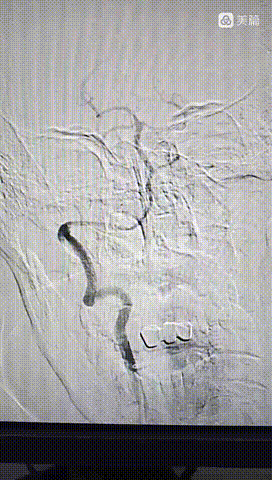

泥鳅导丝导引6FGT68血栓抽吸导管,泥鳅导丝不出头,内芯支持抽吸导管到达V3段。

踹马桶抽吸出小块硬质血栓。